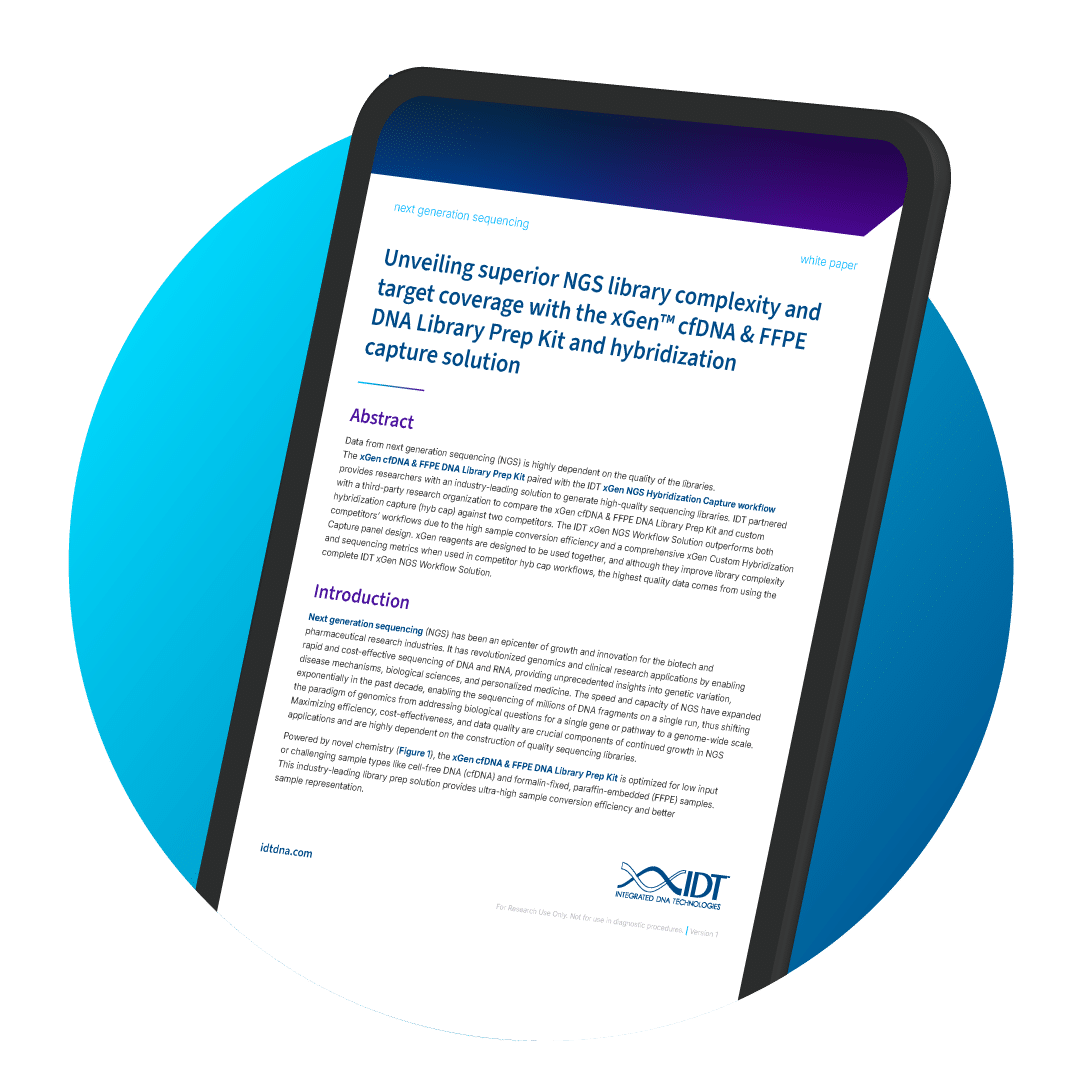

Unlock superior performance with IDT’s xGen cfDNA/FFPE Kit and panels—higher on-target rates, better coverage, and lower duplication than leading workflows.